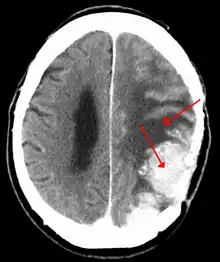

A contrast-enhanced CT scan of the brain, demonstrating the appearance of a meningioma | |

Meningiomas are visualized readily with contrast CT, MRI with gadolinium,[22] and arteriography, all attributed to the fact that meningiomas are extra-axial and vascularized. CSF protein levels are usually found to be elevated when lumbar puncture is used to obtain spinal fluid. On T1-weighted contrast-enhanced MRI, they may show a typical dural tail sign absent in some rare forms of meningiomas.[17]